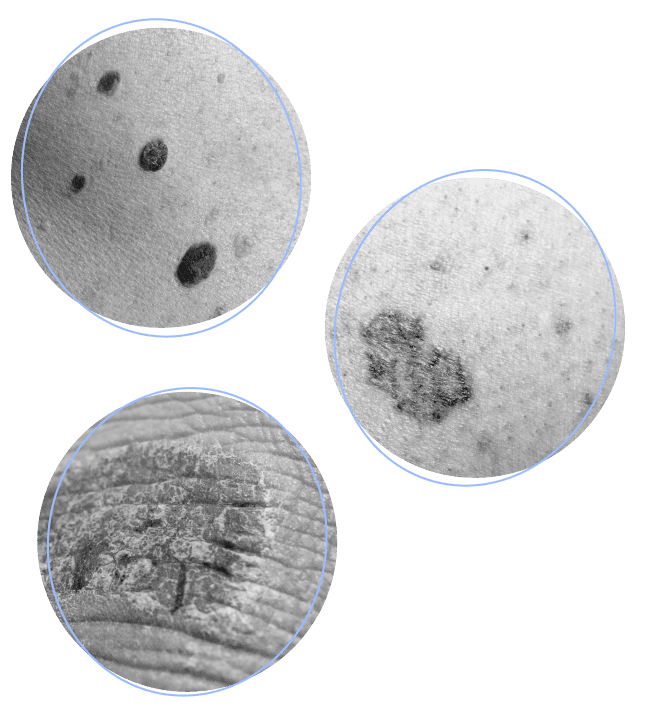

Marks on your skin may be a sign of something more serious

Precancerous marks

Sunspots may be actinic keratoses (AKs). These precancerous spots are caused by years of sun exposure and are extremely common. Nearly 60 million Americans currently live with AKs.

Nonmelanoma skin cancers

Squamous cell carcinoma (SCC) and basal cell carcinoma (BCC) are the 2 most common forms of skin cancer. When they are detected and managed early, they tend to be very treatable over time.

Melanoma

Melanoma is the 3rd most common, and most severe, skin cancer.

Sunspots, which could be precancerous AKs, should be screened early

Advanced basal cell carcinoma is serious, but nonsurgical and nonchemotherapy options exist